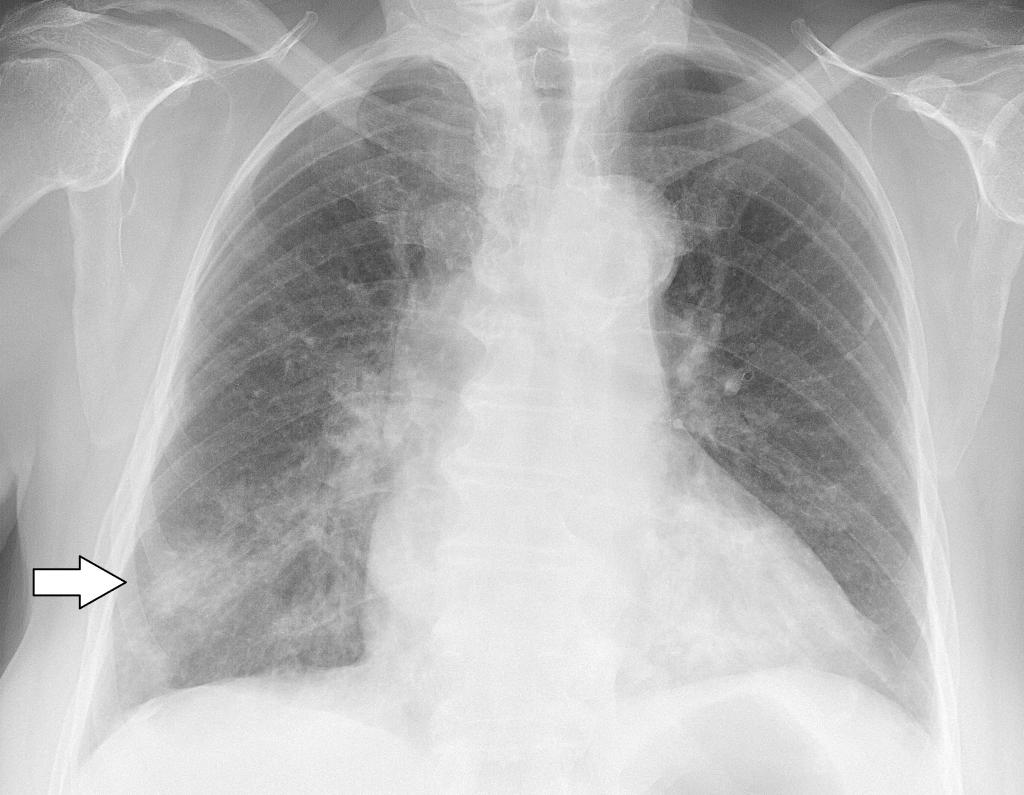

Как и при простой пневмонии, при вирусной форме заболевания, на рентгене видны такие же признаки поражения легких:

- затемнения;

- тени разной формы и размера;

- изменение корней легких.

Вирусная пневмония на рентгеновском снимке выглядит следующим образом: